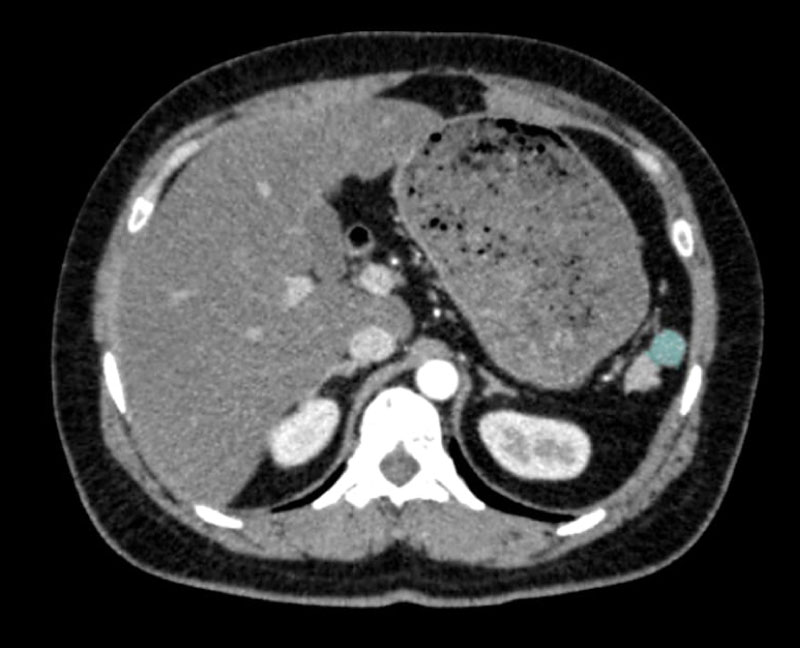

Abdominal USG evaluations performed 6 months post-splenectomy and later 6 years post-splenectomy, did not report presence of an accessory spleen. The third and final abdominal USG of the patient with refractory thrombocytopenia revealed an accessory spleen measuring 1.5 cm (Figure 1). Computed tomography (CT) as well as a magnetic resonance imaging (MRI) performed following the abdominal ultrasonography also confirmed presence of an accessory spleen (Figure 2 and Figure 3). In the case of the patient being presented, the accessory spleen detected in USG, MRI and CT was not observed in 3mCI Tc99m-sulfide colloid scintigraphy. A second splenectomy was planned for removal of the accessory spleen.

Figure 3: Computed tomography (CT) demonstrating accessory spleen. View Figure 3